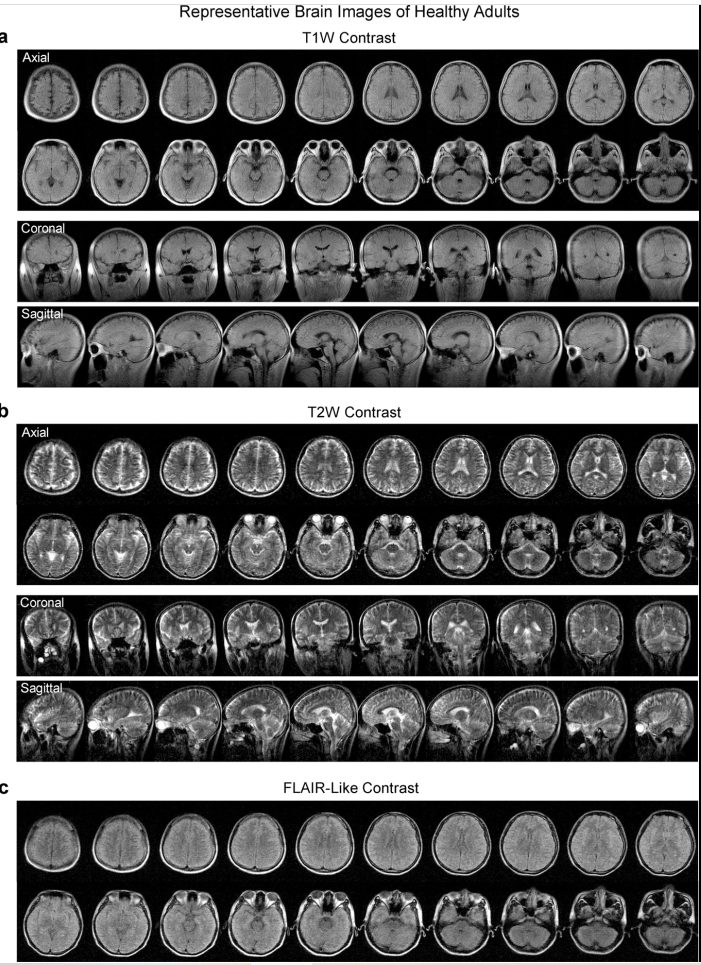

Segundo, foi possível implementar os quatro protocolos para ressonância magnética cerebral clínica: T1W, T2W, FLAIR e DWI. E terceiro, a eficácia para diagnóstico de tumor cerebral e acidente vascular cerebral foi, até certo ponto, comparável a de um scanner 3T (modelo padrão utilizado na clínica).